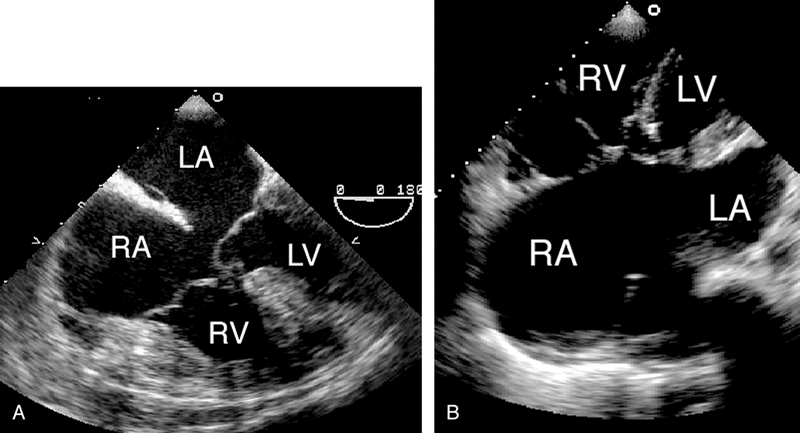

فحوصات تشخيصية لبعض امراض القلب والشرايين التاجية